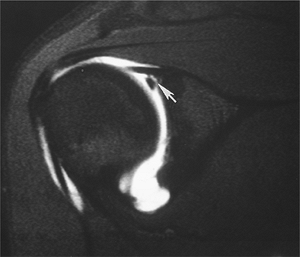

![]() |

FIGURE 7-32 Coronal fat-suppressed arthrogram image demonstrating a Type 3 SLAP tear (arrow).